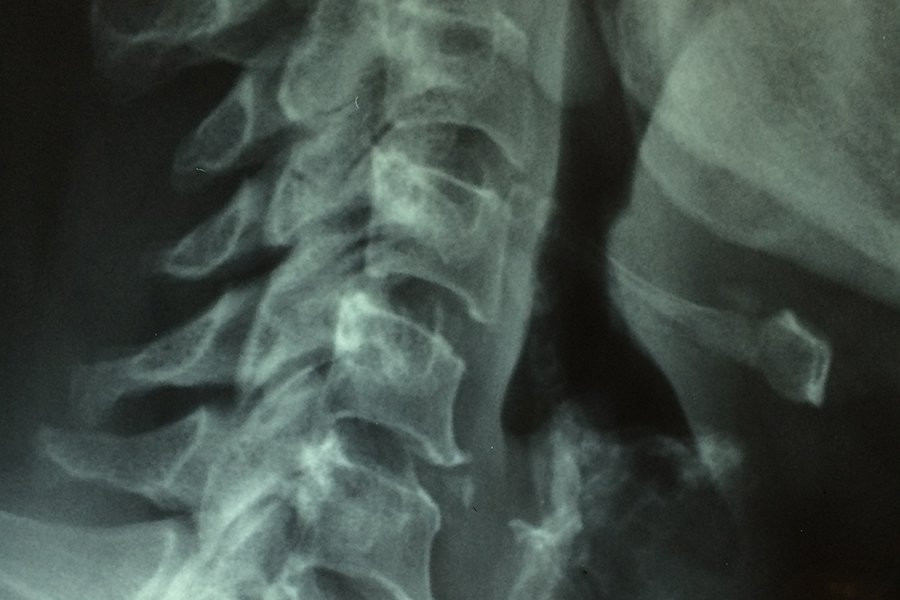

Фото из открытых источников

Новое исследование показывает, что образование рубцов после травм спинного мозга является более сложным процессом, чем считалось ранее. Ученые определили два типа периваскулярных клеток, которые играют ключевую роль в формировании рубцовой ткани, которая препятствует регенерации нервов и функциональному восстановлению. Эти результаты, опубликованные в журнале Nature Neuroscience, также актуальны для других травм головного и спинного мозга и могут привести к разработке таргетной терапии для уменьшения рубцов и улучшения результатов.